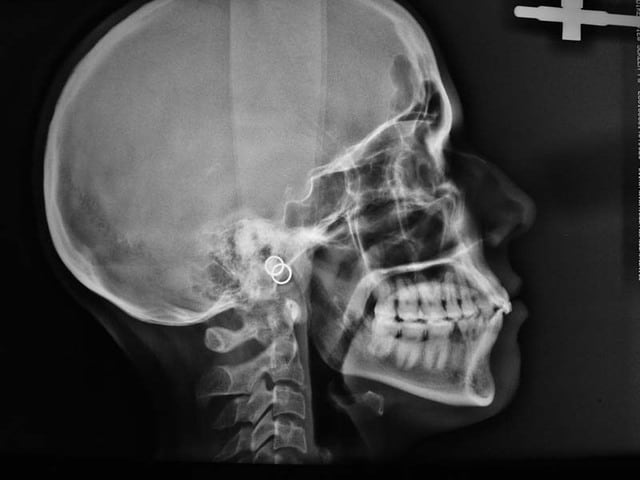

voici les Rx.

Au départ, il existait des Pbs. des deux cotés, inégalement répartis. maintenant le coté D. est bien, mais que dire du coté G. et du bloc Ant. qui évolue vers une Cl. II. 2, malgré une contention Inf.

comme quoi un TTT. ODF. peut présenter un joli résultat sur un secteur et désorganiser les autres secteurs

la contention Inf. ne peut pas empêcher l’évolution défavorable de ce cas

heureusement, je n’ai pas de Pbs. de d’ATM.

si j’arrive à redresser les arcades (reformage) et si je réouvre au niveau de 35, le Pb. se posera alors du remplacement de cette dent

cela fait beaucoup de si

voilà comment avec une extraction, on transforme un cas, au départ relativement simple, en cas compliqué

@+ Bjc.